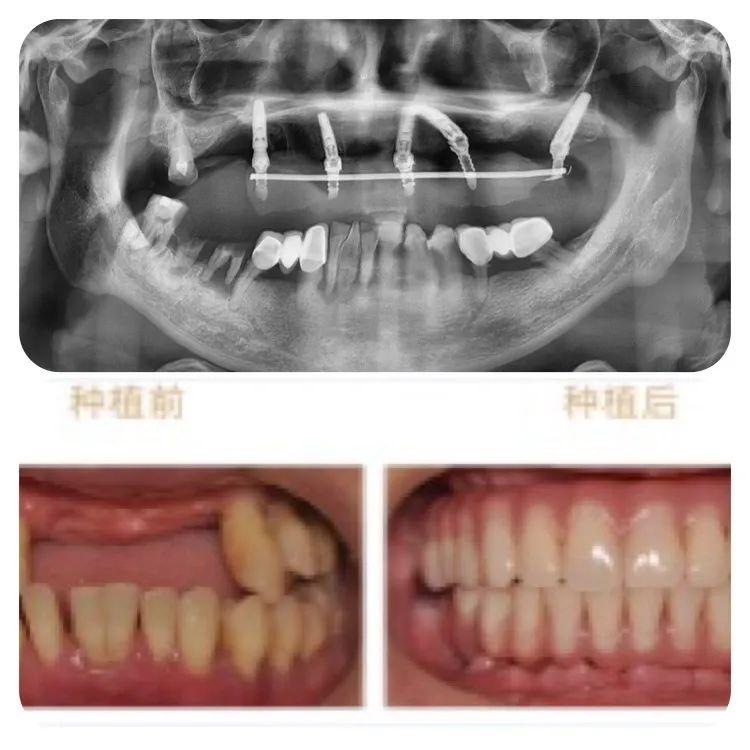

此次成功種牙的78歲高齡的老人,不但同時患有高血壓、心臟病及糖尿病,口腔條件也不容樂觀:因外傷引起牙缺失2年,有較嚴重的牙周炎,是典型的高齡疑難種牙案例。

針對老人的口腔條件,重慶泰康拜博口腔VIP種植工作室通過3D數(shù)字化種植設(shè)計系統(tǒng)為他個性化計了帶1顆穿翼板種植的負重種植牙方案,即拔即種,全口牙在1天之內(nèi)完成了種牙、戴冠全過程,手術(shù)完成后帶上臨時牙冠,牙齒就已經(jīng)可以正常使用。

術(shù)后1周復查,通過口腔CT檢查,可以看見老人的種植牙、穩(wěn)固。老人自己也描述,他在種牙的時候感覺輕松快速,幾乎沒有痛感,打個盹的功夫,牙齒就種好了。